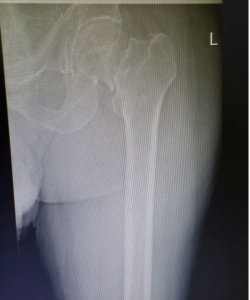

- Femur Fractures.